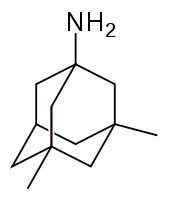

Medications used to treat the cognitive symptons of Alzheimer's disease rather than the underlying cause include: four acetylcholinesterase inhibitors (tacrine, rivastigmine, galantamine, and donepezil) and memantine, an NMDA receptor antagonist. The acetylcholinesterase inhibitors are intended for those with mild to severe Alzheimer's, whereas memantine is intended for those with moderate or severe Alzheimer's disease.[119] The benefit from their use is small.[172][173][174][13]

Glutamate is an excitatory neurotransmitter of the nervous system, although excessive amounts in the brain can lead to cell death through a process called excitotoxicity which consists of the overstimulation of glutamate receptors. Excitotoxicity occurs not only in Alzheimer's disease, but also in other neurological diseases such as Parkinson's disease and multiple sclerosis.[180] Memantine is a noncompetitive NMDA receptor antagonist first used as an anti-influenza agent. It acts on the glutamatergic system by blocking NMDA receptors and inhibiting their overstimulation by glutamate.[180][181] Memantine has been shown to have a small benefit in the treatment of moderate to severe Alzheimer's disease.[182] Reported adverse events with memantine are infrequent and mild, including hallucinations, confusion, dizziness, headache and fatigue.[183][184] The combination of memantine and donepezil[185] has been shown to be "of statistically significant but clinically marginal effectiveness".[186]